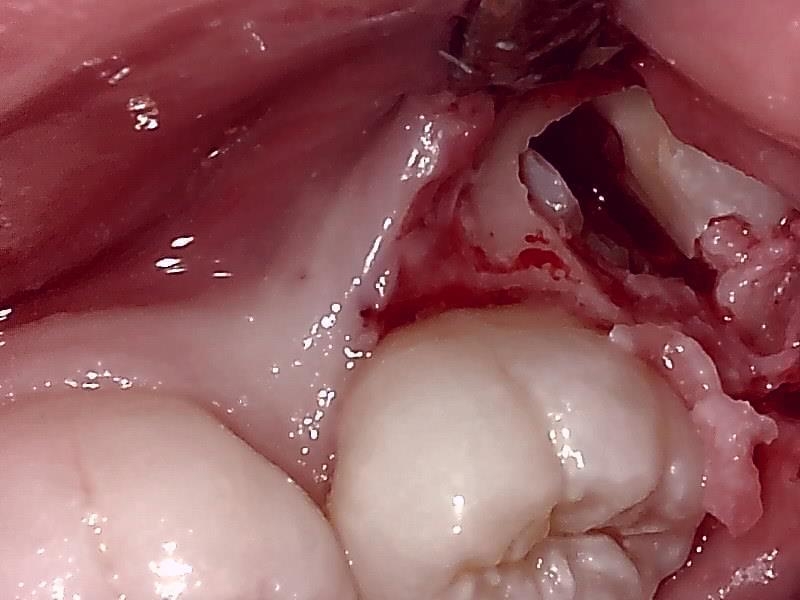

歯牙を分割して抜去する。

侵襲を最小限に軽減して分割して抜去する。

分割して隙間から抜去する。